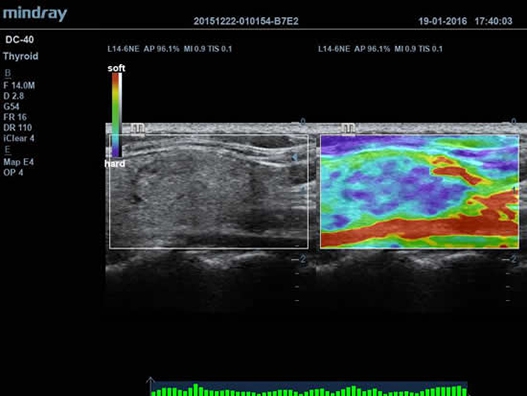

• Функция эластографии Natural Touch позволяет проводить эластографические исследования.

Natural Touch Elastography: